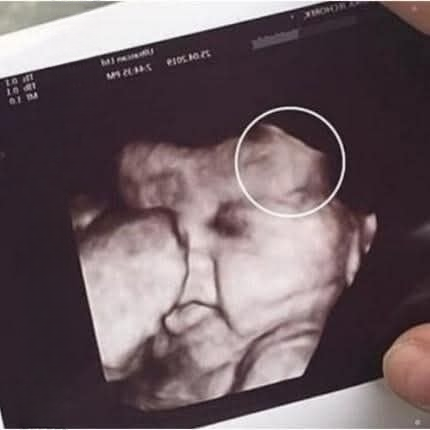

3. The Moment That Sparked Fear

The tension intensified when the technician adjusted the ultrasound probe to focus on the baby. For many, this is the highlight of the appointment—a chance to see the tiny heartbeat, the subtle movements, or the developing features of the child.

However, for the mother in this scenario, the images on the monitor provoked visible fear. She recoiled slightly, her expression showing shock and concern. The technician, trained to respond calmly, paused to adjust the settings and ensure clarity. In that brief moment, the room felt heavy with anticipation. The daughter, trying to maintain composure, experienced heightened stress as her mother’s unease amplified the emotional atmosphere.

The technician then gently explained that the scan had revealed an unclear area requiring further evaluation. No definitive conclusions were made, and reassurance was provided that ambiguous images are not unusual.